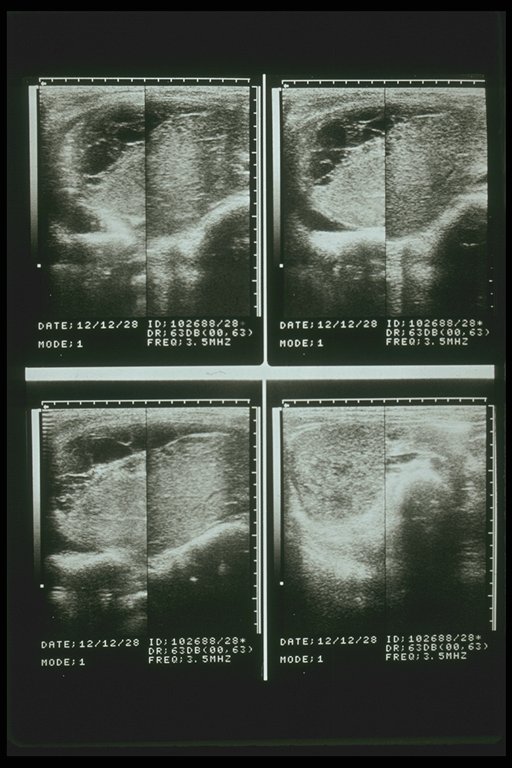

Subcapsular hematoma of the right lobe liver demonstrated by ultrasonography, a low echoic area is characteristic finding

Intrahepatic hematoma of the right lobe liver demonstrated by ultrasonography